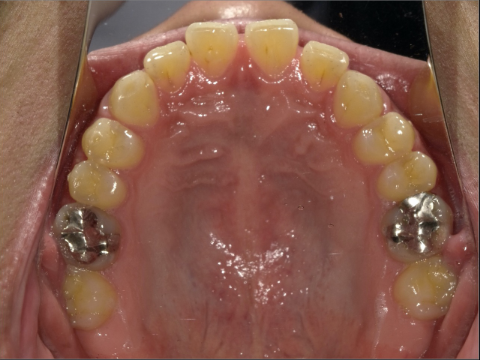

ご年齢 35歳男性 治療期間 2022/08/22〜2023/03/24(1年5ヶ月)

診断 110,000円(税込) アライナー 550,000円(税込) リテーナー 55,000円(税込)

ご年齢 35歳男性

治療期間 2022/08/22〜2023/03/24(1年5ヶ月)

診断 110,000円(税込)

アライナー 550,000円(税込)

リテーナー 55,000円(税込)

BEFORE

AFTER